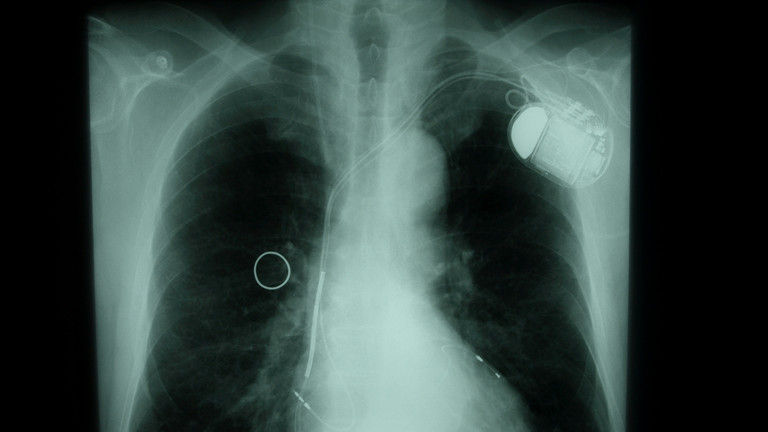

Your benefits range from receiving a cardiac device such as a pacemaker or defibrillator to receiving cardiac resynchronization treatment (CRT) or implantation of an artificial heart (LVAD – left ventricular assist device). In 2018, the Albertinen Heart and Vascular Center located at the Albertinen Hospital was certified as Hamburg's first "National Heart Failure Unit Center".

Pacemaker implantation: 1-chamber, 2-chamber, 3-chamber (CRT), wireless pacemaker ("leadless" pacer)

-

Defibrillator implantation: 1-chamber, 2-chamber, 3-chamber (CRT), subcutaneous defibrillator (S-ICD)